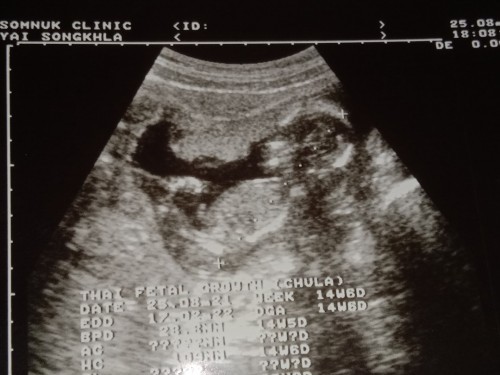

ซาวตอน14วีค ตอนนี้18วีคแล้ว รอลุ้นเพศจ้า